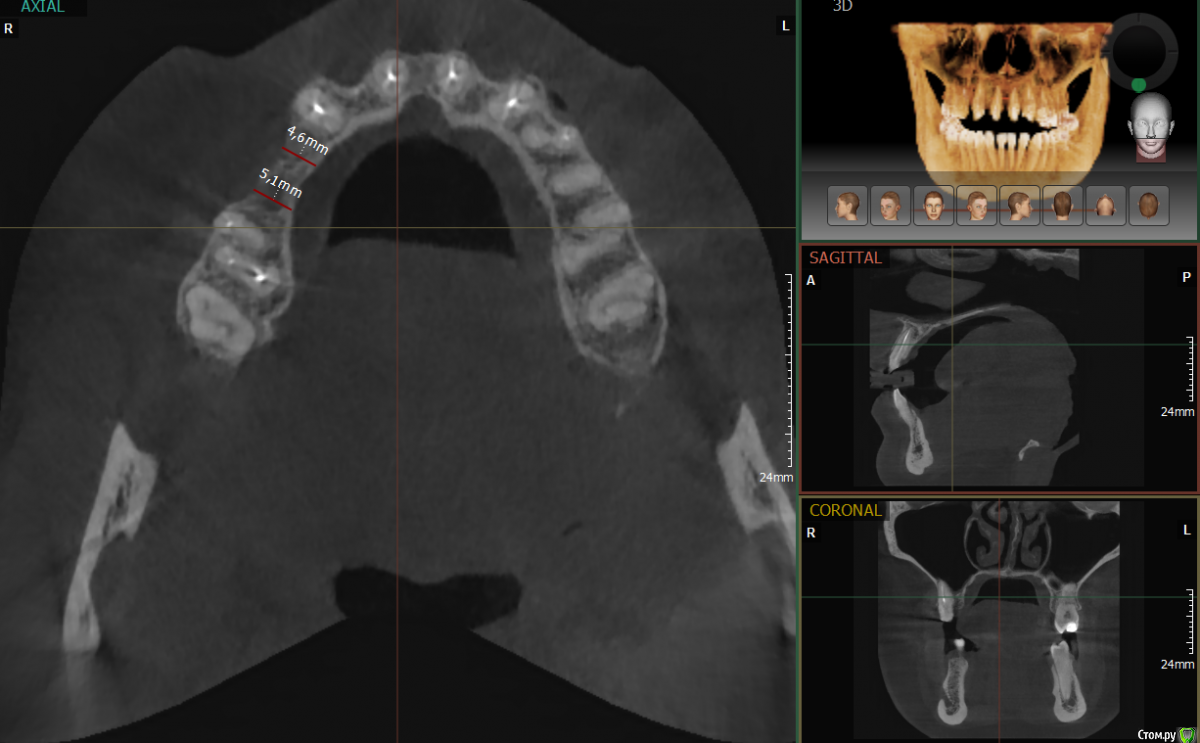

AlexanderGudkov Опубликовано 20 мая, 2017 Поделиться Опубликовано 20 мая, 2017 А какой диаметр имплантатов? Ссылка на комментарий

Петр Бриньковский Опубликовано 20 мая, 2017 Автор Поделиться Опубликовано 20 мая, 2017 А какой диаметр имплантатов?4.0 Ссылка на комментарий